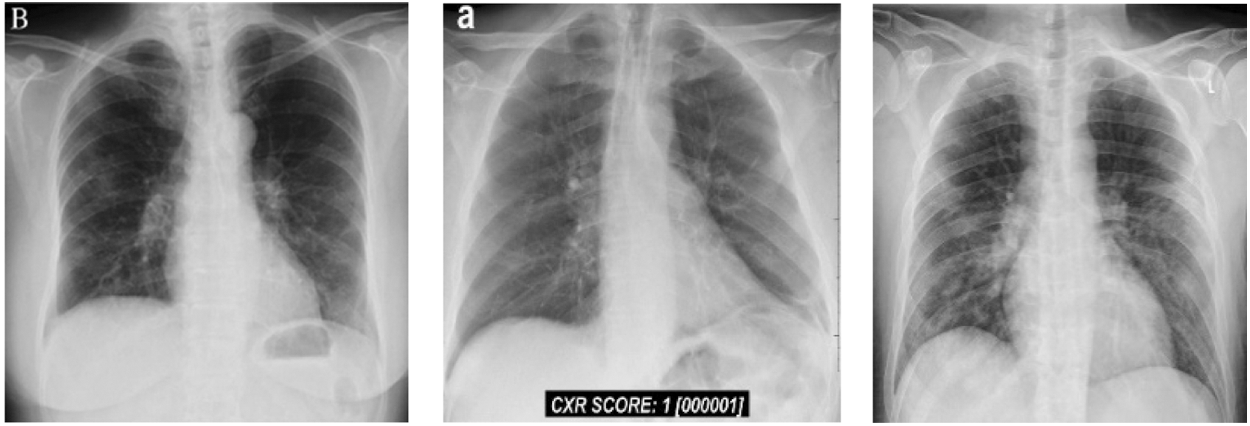

In this group, we have total 146 cases are considered as they belong to 0–6 day’s offsets of symptoms. It means, Group B belong to the period of the first six days of, Fig. 4 shows Chest X Ray Images of Group B.

Figure 4: Chest X-ray images of Group B (patients of 0–6 days offset of symptoms)